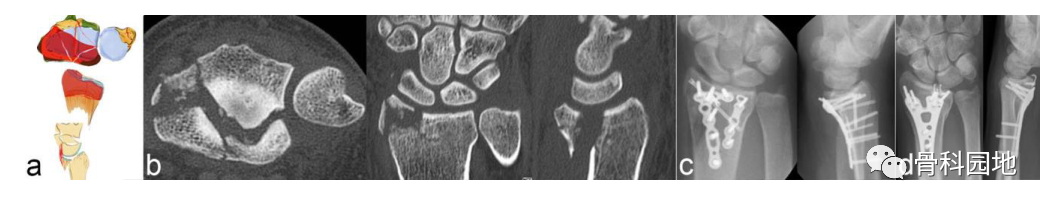

2、掌侧关节骨块

注:可以是大的或较小的边缘碎片。可能发生掌侧脱位,而背侧韧带保持完整 (a)。掌侧骨块:重要的尺桡韧带和尺腕韧带的起源 (b)。向掌侧脱位(c)。掌侧骨折从尺侧延伸到桡侧(d)。在 X 光平片上很容易忽略小的掌侧尺骨骨块,但轴位 CT 扫描容易显示该骨块 (e)